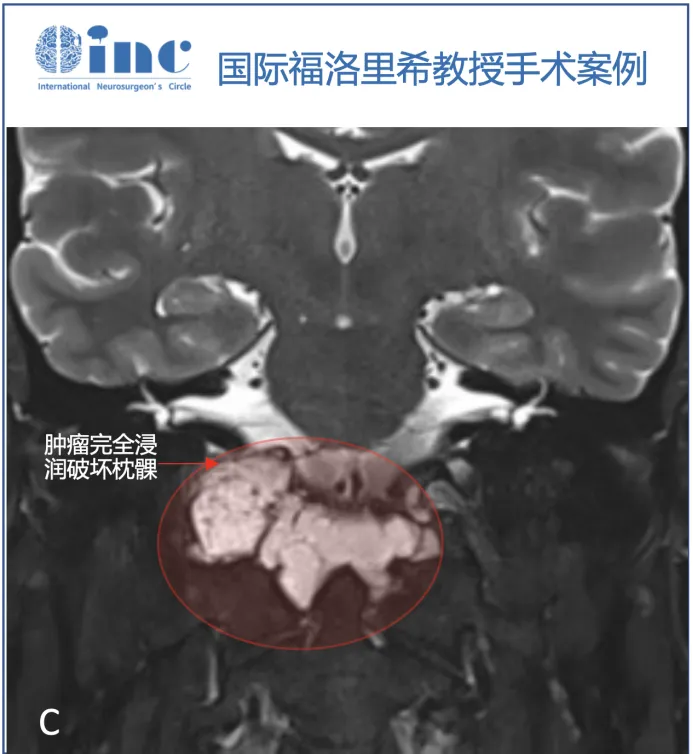

脑MRI检查显示颅颈交界处巨大轴外病变,提示脊索瘤,T1WI等强度,T2高强度,不均匀增强,以右侧岩斜坡软骨联合为中心,向下延伸至颅颈交界处,硬膜内延伸至Luschka孔,压迫脑干。肿瘤压迫小脑的最后部分也有增强,提示该部分肿瘤的颅底浸润和颅底血管化。右侧枕髁被肿瘤浸润并完全占据。由于肿瘤向外侧、硬膜内浸润生长,血管包膜和颅底浸润,内镜下鼻内入路被认为风险较高,实现完全切除的机会有限。

▼T2序列(B、C)上的多小叶形态和病变的生长模式,考虑脊索瘤。右侧枕髁被肿瘤完全破坏(C)。